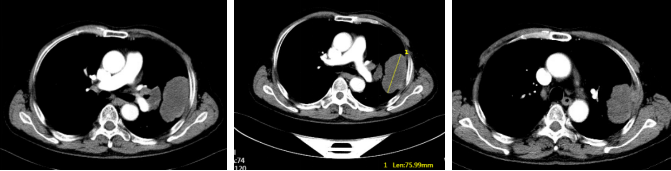

● 2024年12月26日颈胸腹盆CT增强:左肺上叶占位性病变(74mm),考虑癌,侵犯胸壁,伴左肺门淋巴结转移。

胸部腹部增强CT(2024年12月26日)

● 2025年3月19日颈胸腹部CT增强:左肺上叶病灶及左肺门淋巴结较前明显缩小。总体评效:PR(缩小38%)。

● 2025年6月19日颈胸腹增强CT增强:左肺上叶病灶及左肺门淋巴结较前缩小。总体评效:持续PR(缩小49%)。

胸部腹部增强CT